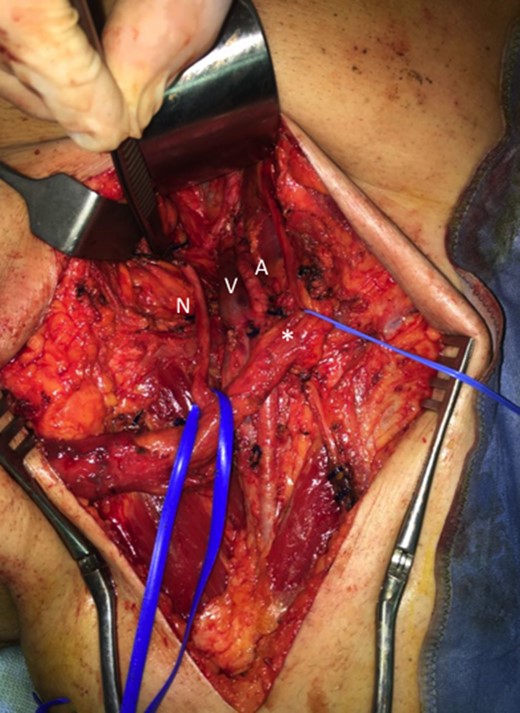

Then a right mastectomy with third level axillary lymphadenectomy, for sentinel lymph node positivity; removal of the left abdominal mass with resection of the band of external oblique muscle and of the infiltrated anterior inguinal wall; lymphadenectomy of the external and common left iliac artery; deep and superficial left inguinal lymphadenectomy (Fig. 2) were performed. Reconstruction of the abdominal band and of the inguinal canal wall was obtained using a GORE® BIO-A® prosthesis (Fig. 3).

Inguinal region after linfoadenectomy (N, nerve; V, Vein; A, Artery; *spermatic cord).